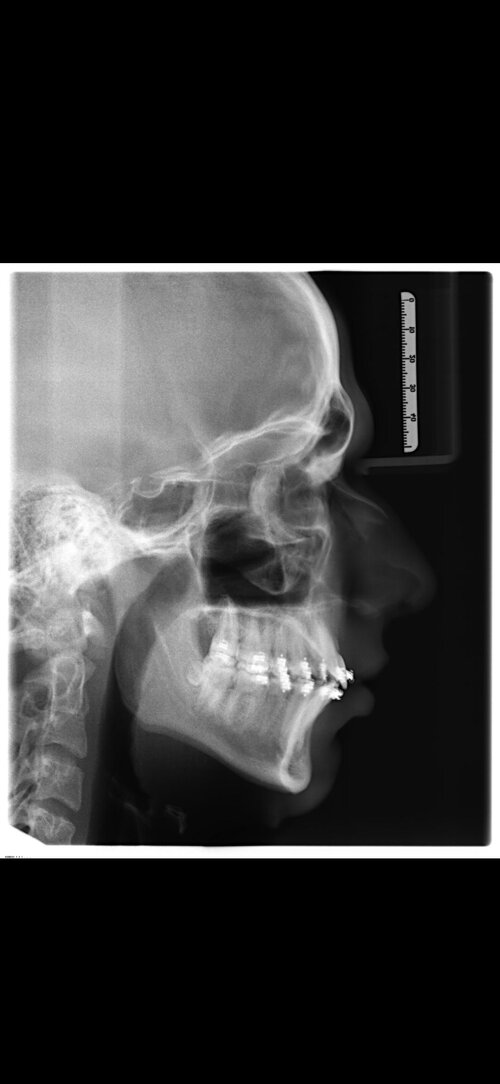

I'm getting bimax in 6 days (I'm 17 years old) performed by Dr Dr Kater (Germany). He's a rather conservative surgeon, but i've heard many good stories and he's very experienced. My concern is: I don't have any exact movements yet, i'll get to talk to him personally one day before the surgery, but i just have a "round about" plan right now. Is that a big problem or would you say the councellingsession on tuesday is enough? Like i said he's a very competent surgeon but i'm still not 100% sure if it's the right choice. Any thoughts on this?

My base btw:

My base btw: